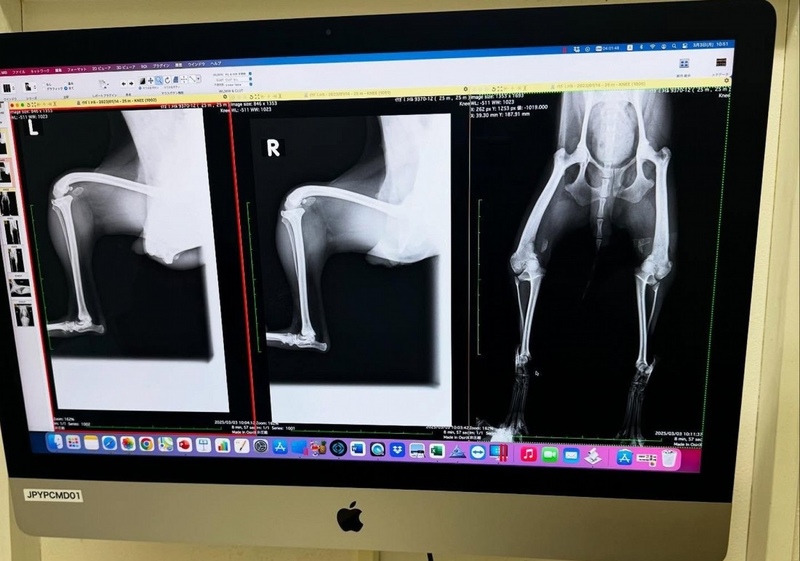

• 膝蓋骨脱臼を放置されたままの子

先天性疾患を抱えた子には、CTやMRIなどの精密検査を行い、正確な診断をつけなければなりません。